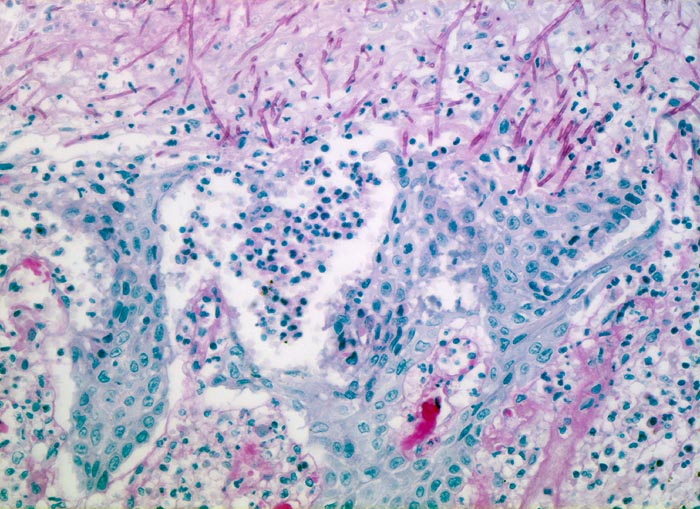

Soorösophagitis

Entzündung infektiös

Oesophagus

Erodierte Schleimhaut mit regeneratorischen Epithelatypien (vergrösserte, leicht polymorphe Kerne mit vergröbertem Chromatin, wenig Zytoplasma). Zwischen den Epithelinseln dichte Infiltrate neutrophiler Granulozyten. PAS positive Soorpseudohyphen infiltrieren das erodierte Epithel.

Mann, 75 Jahre, mit bekanntem multiplen Myelom. Autopisepräparat. Progrediente Dysphagie.

Histologie

200